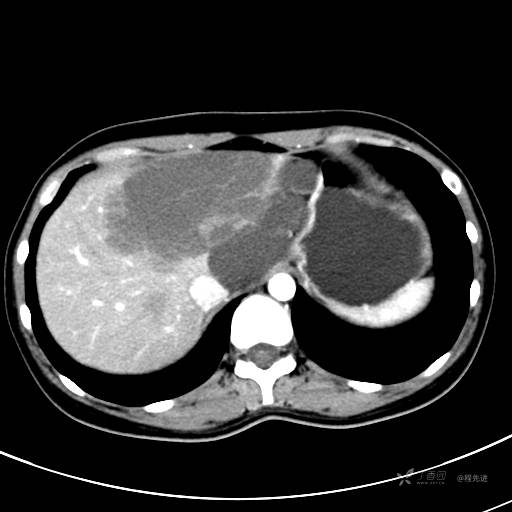

CT平扫+增强,每个序列3张图

CT值 平扫48HU 动脉期66HU 静脉期68HU 延迟期62HU